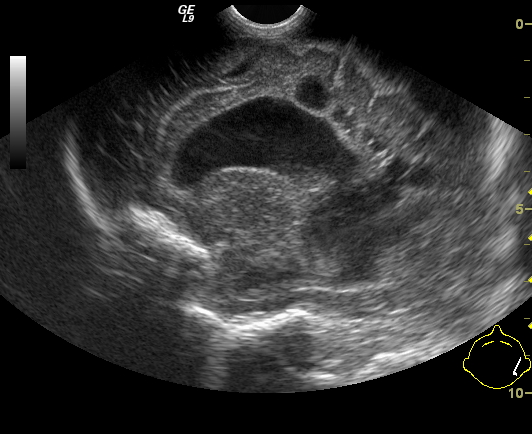

Invagination. A distal intestinal loop invaginating to a proximal intestinal loop can result in a mechanical intestinal obstruction, and cause ischemic damage. It most frequently occurs in infants (3-24 months) with recurring, colic-like complaints, distended intestines, a palpable mass and with frequent vomiting and bloody stool. Invagination requires immediate diagnosis and desinvagination. US exam reveals the invaginated intestines as a “target” sign in axial cross section and looks like a “pseudokidney” in longitudinal cross section. The therapy is hydrostatic or pneumatic desinvagination. Perforation and/or peritonitis are absolute contraindications to these procedures. Hydrostatic desinvagination can be performed under fluoroscopy or with US guidance and is considered successful if air or the contrast material appears in the terminal ileum and the invaginated loop disappears. If these efforts do not succeed, surgical desinvagination is needed.

17. “Target” sign. Invagination. .